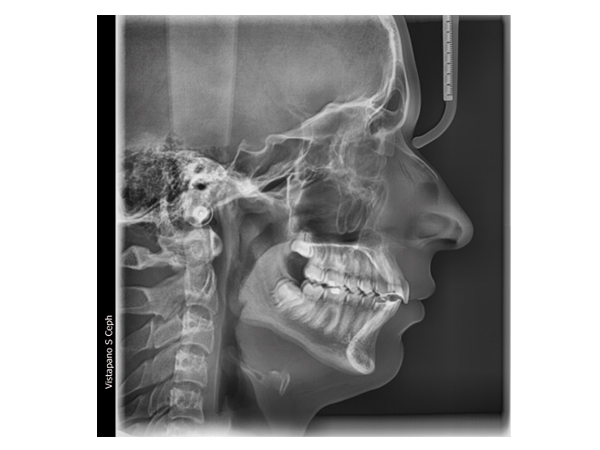

Con el nuevo VistaPano S Ceph se consiguen rápidas tomas tele radiográficas con una extraordinaria calidad de imagen – y esto con unas dosis de exposición lo más reducida posible. La razón son los breves tiempos de escaneado que requieren los sensores lineales, solo 4,1 segundos, y que reducen drásticamente el riesgo de que se produzcan imágenes borrosas debidas al movimiento del paciente. Precisamente con niños, en el campo de la ortodoncia, esta combinación de dosis radiográfica reducida y breves tiempos de escaneado representa una ventaja considerable. Dado que ya están integrados en el aparato dos sensores High-End-CsI para las radiografías panorámicas y la función cefalográfica, se elimina el largo cambio de conexión del sensor , y así el riesgo de sufrir averías. Todo esto convierte a VistaPano S Ceph en la solución radiográfica ideal para la ortodoncia, la cirugía oral y maxilofacial. Además, VistaPano S Ceph le ofrece todas las funciones y ventajas de VistaPano S.

- Muy rápido escaneo en 4,1 segundos (cabeza lat.)

- Calidad de imagen extraordinaria

- Exposición reducida

| Tiempos de escaneado programas cefalográficos | Toma cabeza lateral. En modo de escaneado rápido: 4,1 seg. |